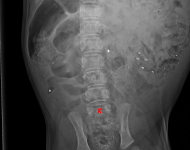

páteř LL

páteř VD

typ 1 I

typ 1 II

typ 3 u sedmiletého křížence